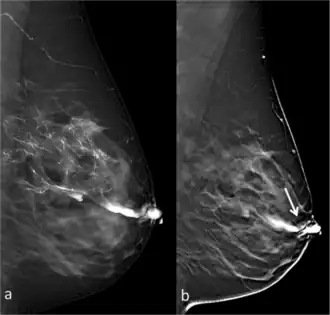

![]() Full-field digital (FFD)-galactography (left) and Digital breast tomosynthesis (DBT)-galactography (right) showing intraductal papilloma. | |

Galactography or ductography (or galactogram, ductogram) is a medical diagnostic procedure for viewing the milk ducts. The procedure involves the radiography of the ducts after injection of a radiopaque substance into the duct system through the nipple. The procedure is used for investigating the pathology of nipple discharge.

Galactography is capable of detecting smaller abnormalities than mammograms, MRI or ultrasound tests. With galactography, a larger part of the ductal system can be visualized than with the endoscopic investigation of a duct (called galactoscopy or ductoscopy).